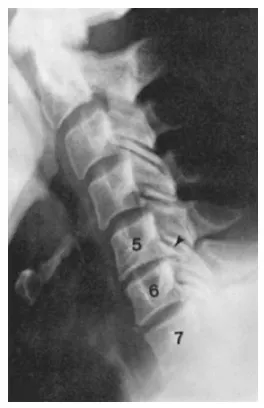

1分鐘秒懂身體症狀-退化性關節疾病/頸椎病變 【標準臨床治療方法】

(Degenerative Joint Disease/Cervical Spondylosis)

你有沒有發現自己開始脖子僵硬、轉動時卡卡的? 甚至感到頸部、肩膀或手臂疼痛,有時還會麻木或無力? 可能還會感到頭暈、頭痛,嚴重時甚至影響日常生活。這些都是頸椎退化的警訊! 頸椎退化會導致關節和椎間盤磨損,骨刺增生,壓迫神經,產生不適。 本篇內容生硬,但可以詳盡告訴你發生什麼問題。